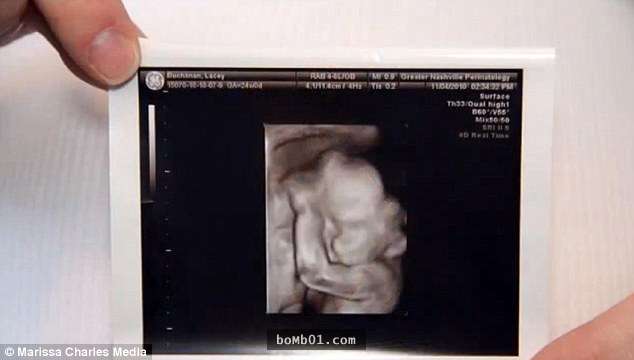

▼Lacey Buchanan是法學院的學生,她15歲時與丈夫Chris Buchanan相遇,兩人21歲步入婚姻殿堂。兩年後她懷上了寶寶,但產檢時的結果卻讓人心碎。

▼醫生告訴他們,這個孩子有羊水帶症候群。這種情況非常罕見,孕婦羊膜破裂的話,破裂處會產生一條帶狀組織,不管它卡在寶寶的哪個部位,都會造成嚴重的影響。Lacey的寶寶面部被破壞,出生後可能失明。